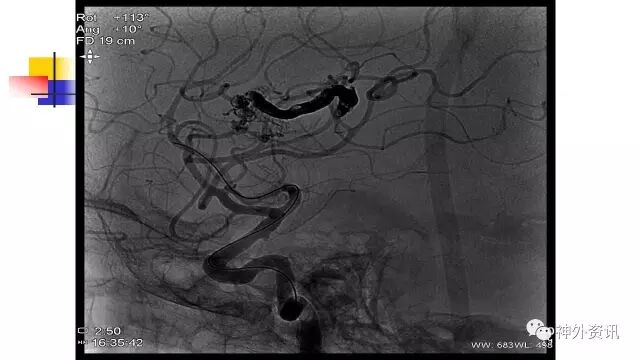

斜位动态